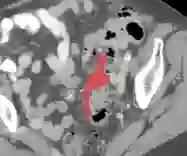

In this paper, we present PRISM, a Promptable and Robust Interactive Segmentation Model, aiming for precise segmentation of 3D medical images. PRISM accepts various visual inputs, including points, boxes, and scribbles as sparse prompts, as well as masks as dense prompts. Specifically, PRISM is designed with four principles to achieve robustness: (1) Iterative learning. The model produces segmentations by using visual prompts from previous iterations to achieve progressive improvement. (2) Confidence learning. PRISM employs multiple segmentation heads per input image, each generating a continuous map and a confidence score to optimize predictions. (3) Corrective learning. Following each segmentation iteration, PRISM employs a shallow corrective refinement network to reassign mislabeled voxels. (4) Hybrid design. PRISM integrates hybrid encoders to better capture both the local and global information. Comprehensive validation of PRISM is conducted using four public datasets for tumor segmentation in the colon, pancreas, liver, and kidney, highlighting challenges caused by anatomical variations and ambiguous boundaries in accurate tumor identification. Compared to state-of-the-art methods, both with and without prompt engineering, PRISM significantly improves performance, achieving results that are close to human levels. The code is publicly available at https://github.com/MedICL-VU/PRISM.